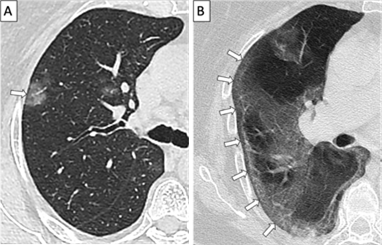

Se muestran imagenes tomograficas de dos pacientes de 65 años con diagnóstico confirmado de COVID-19 mediante prueba molecular (Figura 1), ambos con obesidad. El primer paciente presentó un cuadro leve con fiebre, tos y diarrea; el segundo presentó un cuadro severo con fiebre, tos y disnea. En las imagenes tomograficas de tórax en vista axial, sin uso de contraste en ventana pulmonar, se observa el signo de "preservación subpleural" (flechas blancas). Este signo se define como una región de 1-2 mm de parenquima pulmonar subpleural no opacificado, hallazgo muy sugestivo de neumonia intersticial inespecifica. Se observa tambien en casos de contusión pulmonar, proteinosis alveolar pulmonar y algunas infecciones virales. Recientemente se ha descrito en casos de neumonia por la COVID-19 y ha sido considerado como un signo diagnóstico de esta, por lo que resulta importante su identificación en las tomografias de t6rax de este grupo de pacientes.

We present tomographic images from two 65-years-old patients with COVID-19 (figure 1), confirmed by molecular testing. Both patients were obese. The first patient developed a mild case with fever, cough and diarrhea; whereas the second patient developed a severe case with fever, cough and dyspnea. The non-enhanced axial tomographic images in lung window show the "subpleural sparing" sign (white arrows). This sign is defined as a 1-2 mm region of non-opacified subpleural pulmonary parenchyma and is highly suggestive of non-specific interstitial pneumonia. It is also observed in pulmonary contusion, pulmonary alveolar proteinosis and some viral infections. Furthermore, it has recently been described in COVID-19 pneumonia and has been considered as a diagnostic sign of this disease, making it important to identify and recognize it on chest tomographic studies from this group of patients.